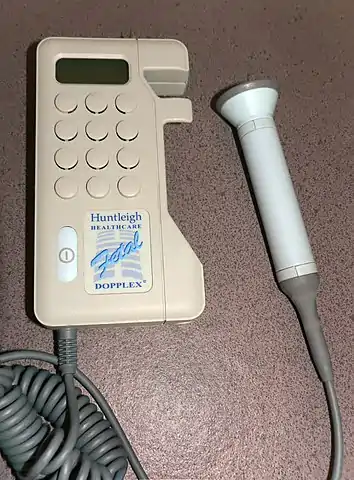

Doppler fetal monitor

Doppler fetal monitors, although usually not technically -graphy but rather sound-generating, use the Doppler effect to detect the fetal heartbeat for prenatal care. These are hand-held, and some models also display the heart rate in beats per minute (BPM). Use of this monitor is sometimes known as Doppler auscultation. The Doppler fetal monitor is commonly referred to simply as a Doppler or fetal Doppler. Doppler fetal monitors provide information about the fetus similar to that provided by a fetal stethoscope.